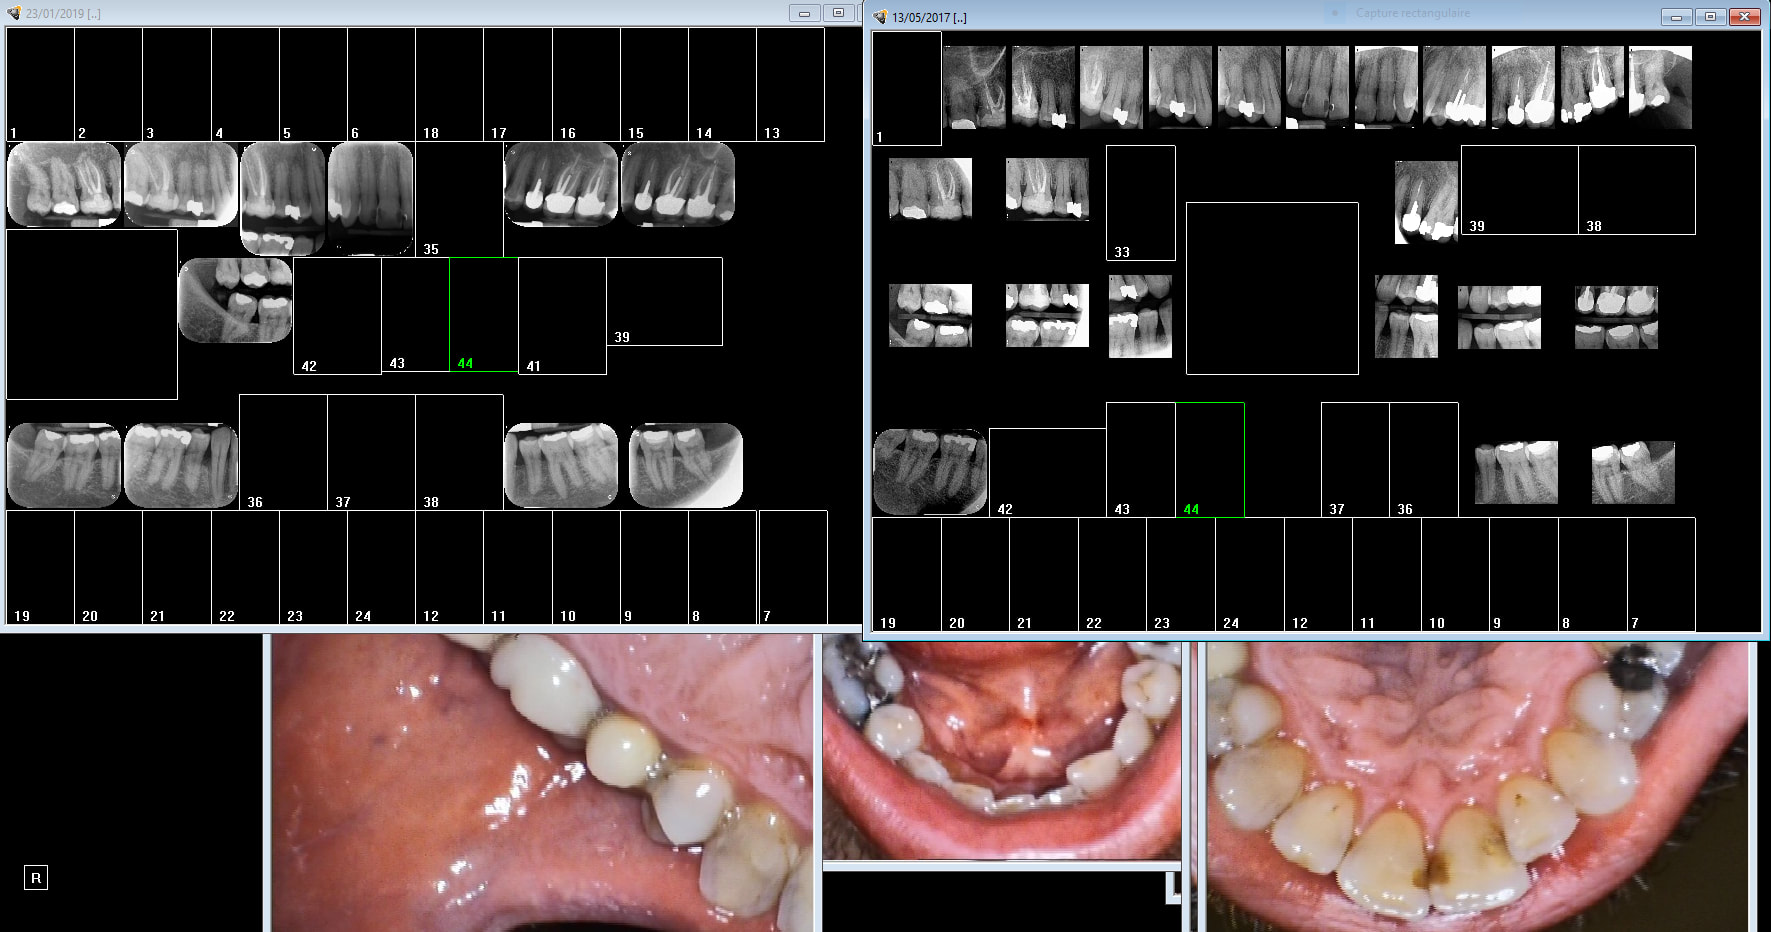

L'imagerie de julie est merdique. L'imagerie CS en revanche c'est de la balle. Je te conseille fortement de l'utiliser avec une passerelle entre julie et CS. Enregistrement par session d'actes ou tu combines photos et radios. Ici " endo taille empreinte 36". Les images apparaitront dans ce classement si je clique sur cette session enregistrée.

Careme 36 chijey - Eugenol